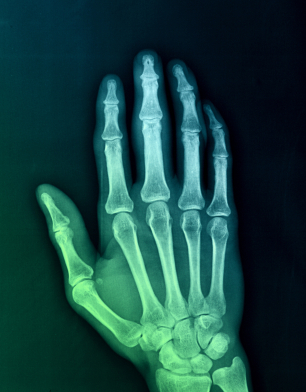

1) What is arthritis?

3) How does the body take attempts to stabilize arthritis?

4) Is there a correlation of x-ray images of arthritis and the severity of the symptoms?

5) What is basilar joint arthritis?